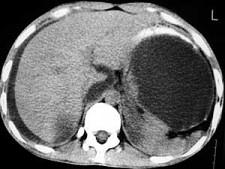

问题 男,33岁,腹部外伤后两月余,腹部疼痛,行CT扫描所见如图,最可能的诊断是 ( )

选项 A、畸胎瘤 B、腹腔包裹性积血 C、慢性胰腺炎 D、胰腺创伤性假性囊肿 E、急性胰腺炎

答案 D